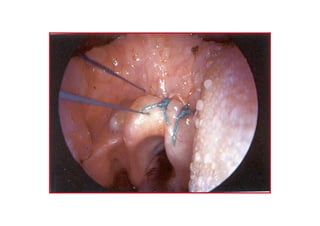

KORDOPEKSKORDOPEKS

TATA posteriorposterior

kk smsm ndanndan

eksizyoneksizyon

VFVF üüst yst yüüzeyindenzeyinden

gegeççen ien i ne ucune ucu

VF alt yVF alt yüüzeyindenzeyinden

2/02/0 polipropilenpolipropilen

KORDOPEKSKORDOPEKS VFVF üüst ystyüüzeyindenzeyinden gegeççen ien i ne ucune ucu

KORDOPEKSKORDOPEKS VF alt yVFalt yüüzeyindenzeyinden gegeççen ien i ne ucune ucu